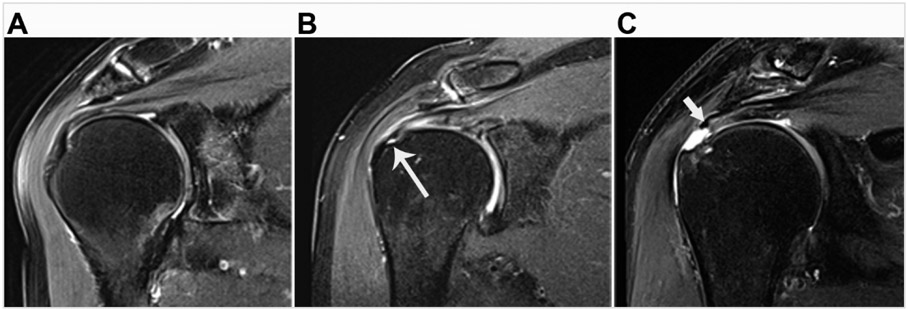

Abstract Image